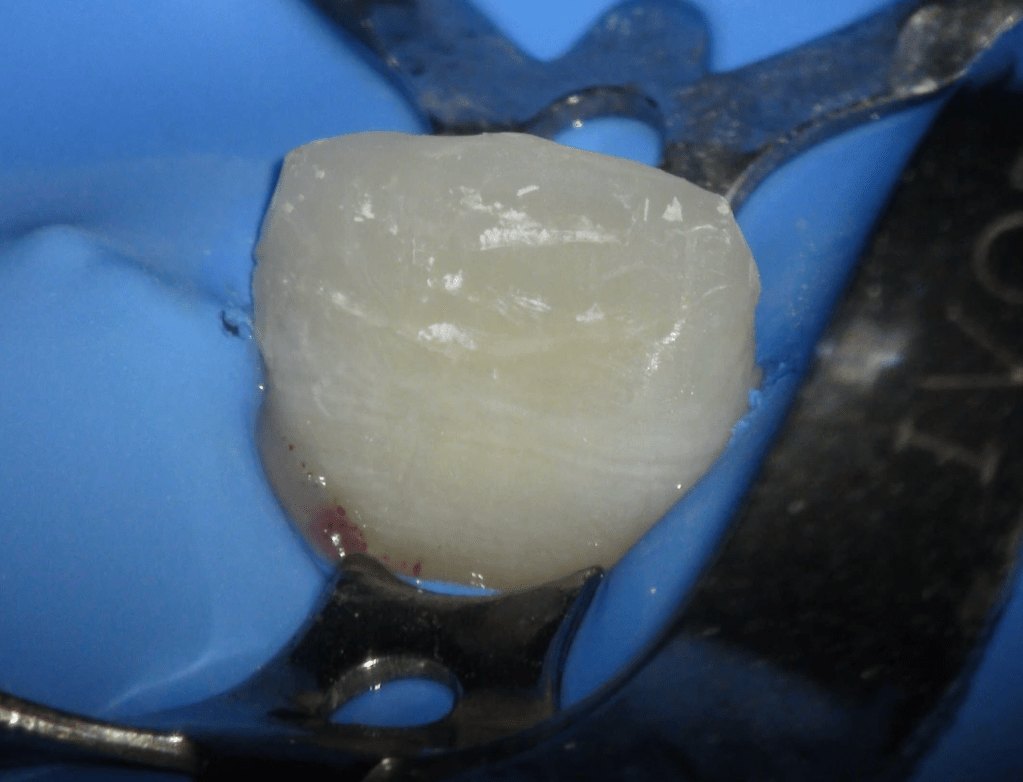

Reco palatina